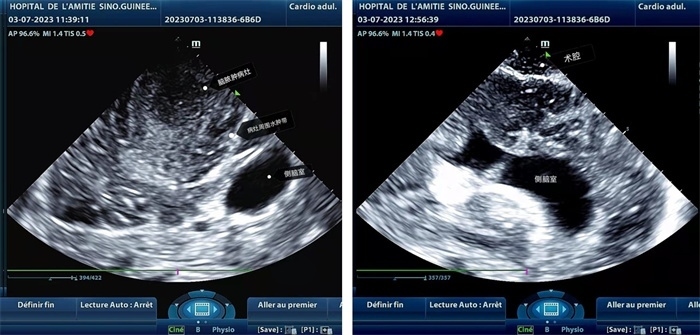

左圖顯示術中超聲見囊實性病變,大小約為4x4x3cm,病灶周圍腦組織水腫明顯;右圖為病灶切除后,術中超聲示術腔無病變殘留

左圖顯示術中超聲見囊實性病變,大小約為4x4x3cm,病灶周圍腦組織水腫明顯;右圖為病灶切除后,術中超聲示術腔無病變殘留。中國第二十九批援幾內亞醫(yī)療隊供圖